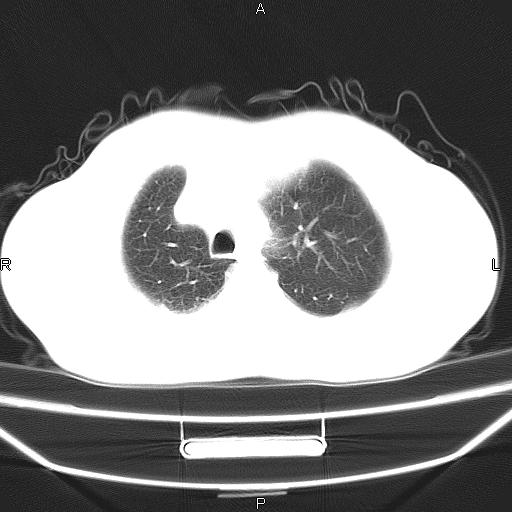

患者,男。50岁。近几日有咳嗽症状,无其他不适,既往病史无,考虑膈疝。请前辈们看看指导指导。

膈膨升,左下肺通气不良,膈肌好像还完整。

考虑左侧膈疝。

左侧膈疝。

符合隔膨升,膈肌较完整。